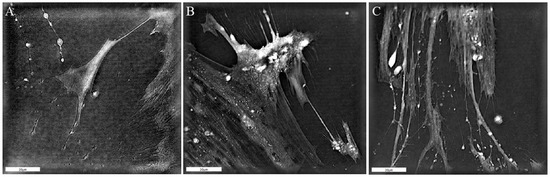

2.5. Three-Dimensional Holotomographic Microscopy

3.2. Patient-Derived CAF Behavior and the Potential to Influence Tumor Cell Growth in HNSCC